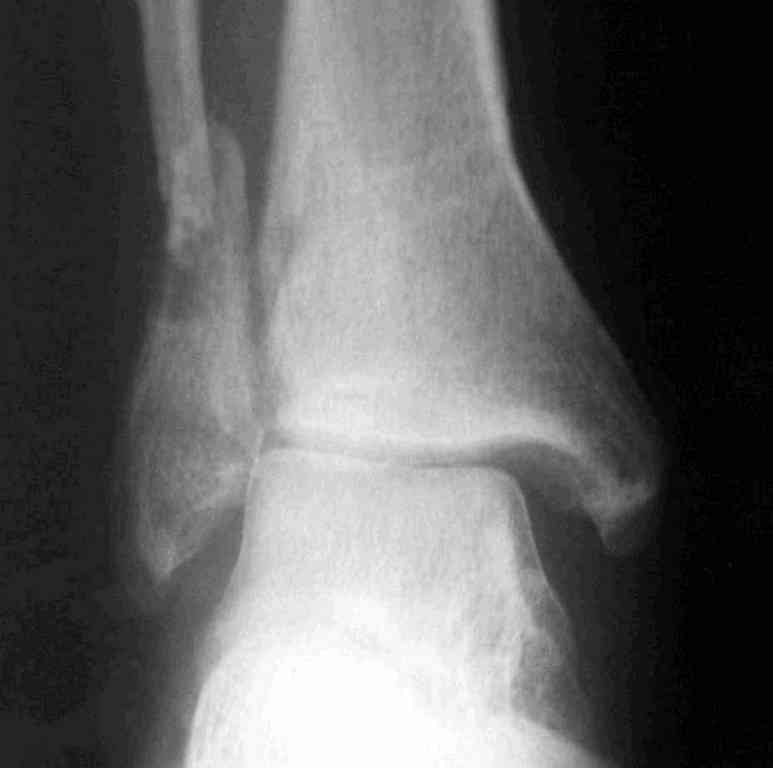

Два примера на снимках.Первый - врач 38 лет, неудачно оперированный в своей больнице с двухлодыжечным переломом, разрывом МБС был повторно оперирован через 8 месяцев. Пытались восстановить длину наружной лодыжки остеотомией, освежили МБС, два месяца функционального лечения без нагрузки на стопу.Сейчас ходит с легкой хромотой, устает к обеду, вальгусное отклонение стопы корригировано супинатором. На Рграммах видны дистрофические изменения латерального эпифиза большеберцовой кости.

Первый снимок через 6 месяцев после травмы, операции остеосинтеза болтом-стяжкой, удаленной по причине нестабильности и наличия свища над металлом.

Вторая пациентка 34 лет, перелом получала в Испании, где от операции отказалась, дома по приезду сняла скотчкаст и лечилась у костоправов, нагрузка с 3 недели. Операция через 3 мес после травмы. Остеотомия м-б кости, фиксация пластиной, восстановление МБС. Так как медиальная лодыжка подтянулась, суставная щель на ЭОП контроле нормализовалась ограничились латеральным доступом. Реконструкцию заднего края не пытались сделать тк там уже прослеживалась консолидация, а сминать эпиметафиз не хотелось. В настоящее время ходит с тростью \три месяца после операции\, сустав нестабилен-слабость дельтовидной связки. Супинатор и плотные кроссовки дают возможность длительно ходить.

Первый снимок сделан в Испании после репозиции, второй через 2 месяца после травмы перед операцией, третий-через 3 мес после операции.